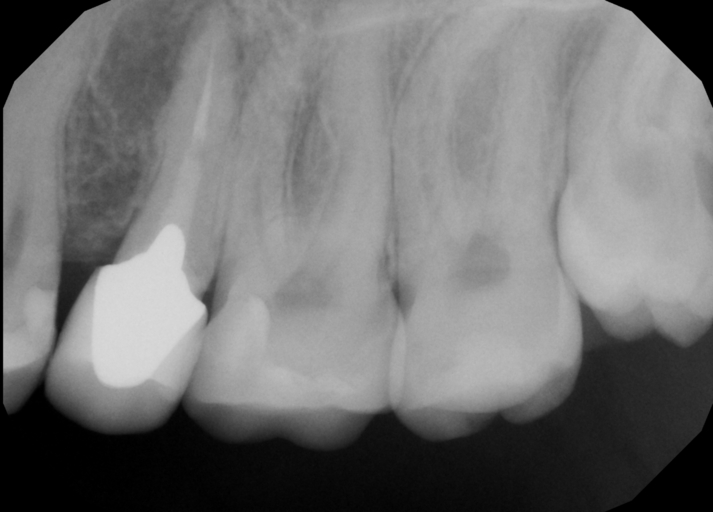

Hello, I had a root canal done on tooth #13 a few years ago, but there was so much decay on the tooth that my dentist had to drill most of the tooth. Because of how little of the tooth is left the crown does not fit correctly, leaving a bit of a gap. The dentist that did the root canal suggested that in the future I get it extracted and get an implant, but also suggested that I get it extracted and instead of getting an implant that I get braces to correct the crowding on my upper and lower teeth and could reduce the need for an implant. I was wondering if this is something that is possible?